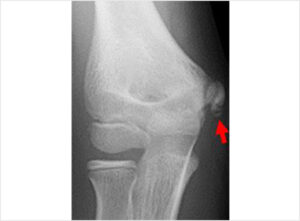

画像引用元:上腕骨内側上顆炎(ゴルフ肘)とは – 森整形外科リハビリクリニック

離断性骨軟骨炎

関節内の軟骨に変化があるとされる状態です。

画像引用元:膝離断性骨軟骨炎とは | 済生会